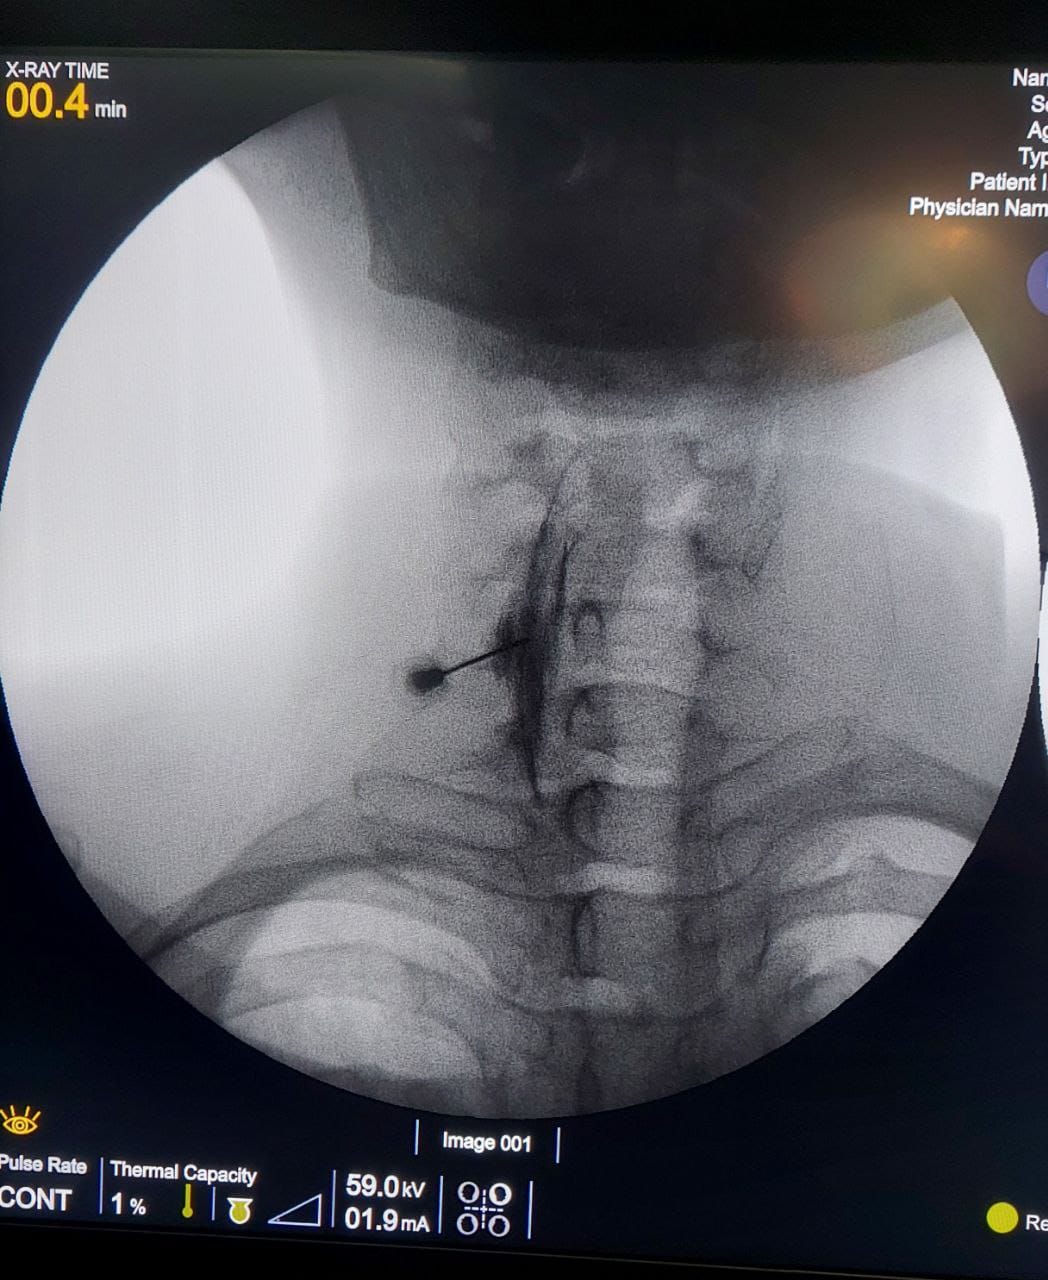

Procedures